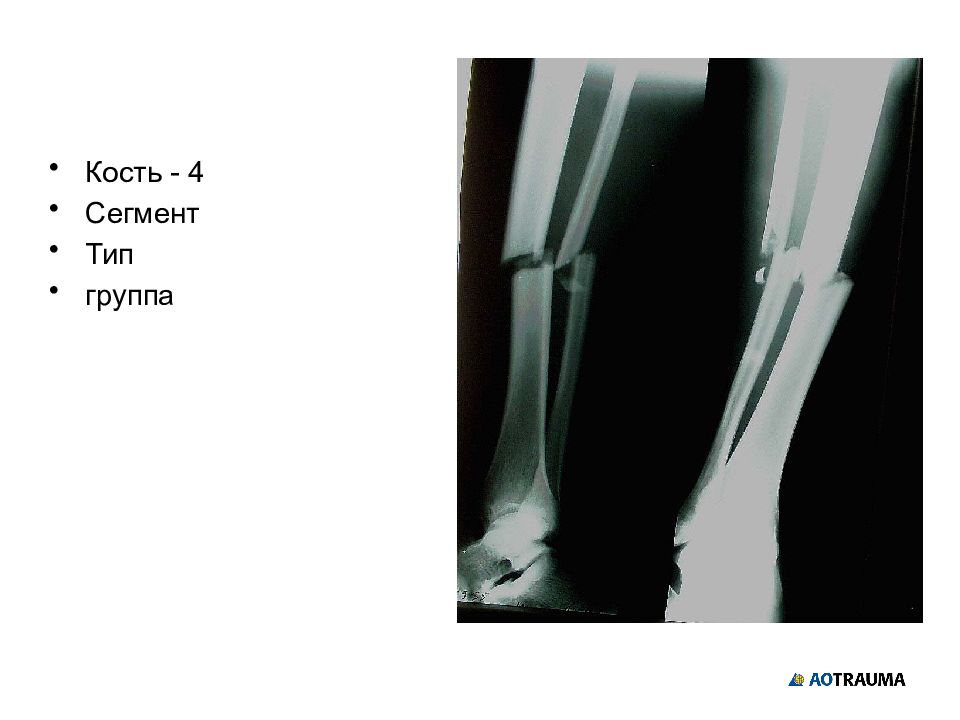

Слайд 26

Кость - 4 Сегмент Тип группа

Изображение слайда

Слайд 27

Кость - 4 Сегмент - 2 Тип Группа

Слайд 28

Кость - 4 Сегмент - 2 Тип - А Группа

Слайд 29

Кость - 4 Сегмент - 2 Тип - А Группа - 3